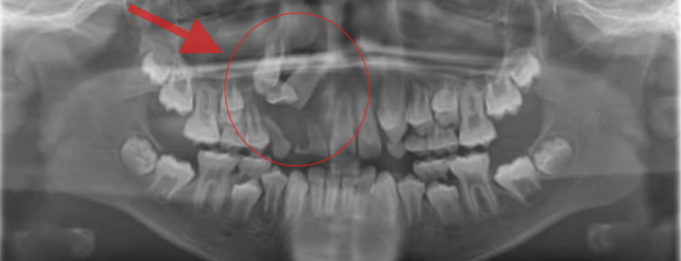

Caso 3

Este caso incluye una radiografía panorámica y dos cortes de imágenes CBCT (tomografía computarizada de haz cónico), los cuales destacan la importancia de la detección temprana. El canino inferior permanente del paciente no pudo erupcionar debido a la presencia de dientes supernumerarios que obstruían su trayectoria eruptiva. Gracias a la identificación oportuna del problema y a la extracción de los dientes de leche supernumerarios, fue posible liberar el trayecto de erupción y permitir que el diente permanente erupcionara de forma natural, evitando así tratamientos más complejos en etapas posteriores.